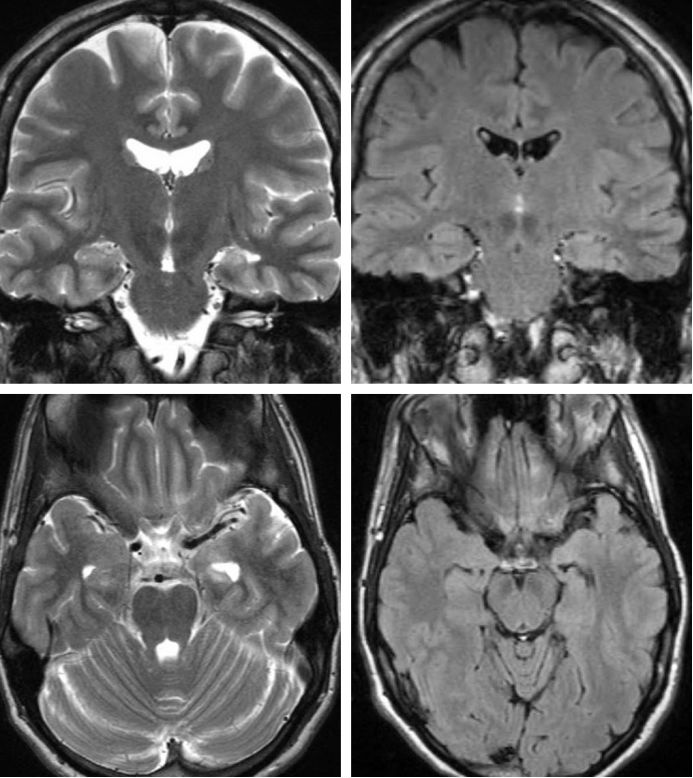

磁共振(MR)成像是TLE的首选影像学检查方法。MR扫描模式应该是整个头颅的薄层高分辨率T1和T2加权像,以及应用梯度回波T2序列来明确是否出血。

如果发现肿块或肿瘤,应使用钆对比剂增强成像,以更好地确定病变性质及显示解剖结构。若怀疑MTLE,则需行冠状位T1加权像、液体衰减反转恢复序列(FLAIR),以及经过海马回冠状位T2加权序列。

颞叶内侧硬化的典型表现是海马萎缩,在FLAIR和T2像呈颞叶内侧高信号。术前MR成像中若有海马萎缩,则颞叶切除术后能明显控制癫痫发作。磁共振成像与本章所讨论的其他诊断模式相结合,对于定位致痫病灶更精确。

图1. 左侧颞叶内侧硬化。注意T2和FLAIR序列显示左侧海马萎缩和明确的高信号。